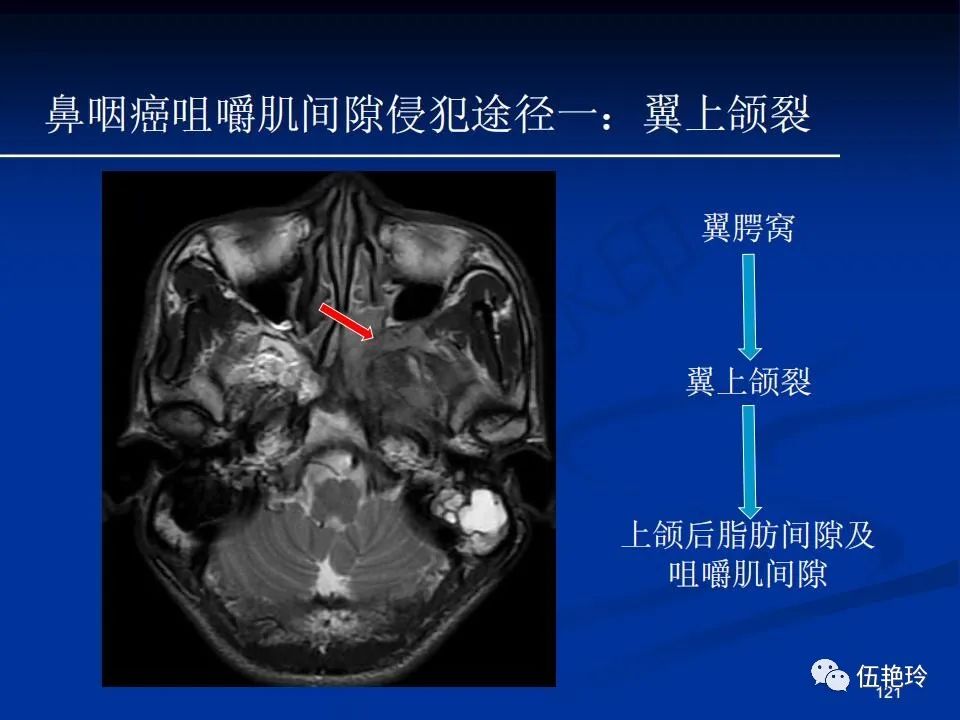

颞下窝与咀嚼肌间隙

2.31 向上颅内:①鼻咽顶壁→破裂孔(岩尖、斜坡)→蝶窦、海绵窦;②鼻咽顶壁→蝶骨基底部→蝶窦、海绵窦;③鼻咽侧壁→茎突前间隙→蝶骨大翼(卵圆孔)→海绵窦;④鼻咽侧壁→茎突前间隙→翼腭窝→ 颞下窝;⑤鼻咽前壁→鼻腔→翼突、翼腭窝→眶下裂→眶尖→海绵窦;⑥鼻咽前壁→鼻腔→上颌窦、筛窦;